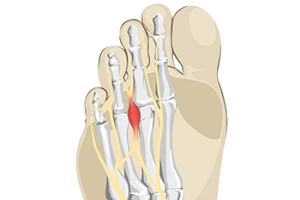

What Is a Neuroma?

The pain from a foot condition that is known as Morton’s neuroma is generally found in the ball of the foot. A neuroma is another name for a pinched nerve or nerve tumor. It is often benign, and can grow and spread to other nerves in the foot. It is an ailment that affects the nerves between the third and fourth toes, and can cause severe pain and discomfort. Many patients describe the pain as feeling like a pebble or marble under the foot, and possibly cause difficulty in completing daily activities. Common reasons for this condition to develop can include frequently wearing high heels, and participating in running and jumping activities that can compress the feet in shoes. Additionally, medical conditions consisting of bunions and hammertoes may lead to getting Morton’s neuroma. A proper diagnosis consists of having a CT scan taken, or possibly an MRI. Many people have found mild relief when specific foot stretches are performed, and it can be beneficial to wear shoes that fit correctly. These types of shoes will have adequate room for the toes to move freely in, and this can help to achieve full range of motion and flexibility. Morton’s neuroma can be painful, and can hinder the ability to complete daily tasks. If you have pain in this part of your foot, it is suggested you consult with a podiatrist who can accurately diagnose and treat Morton’s neuroma.

Morton’s neuroma is a very uncomfortable condition to live with. If you think you have Morton’s neuroma, contact one of our podiatrists of Lexington Foot and Ankle Center, PSC. Our doctors will attend to all of your foot care needs and answer any of your related questions.

Morton’s Neuroma

Morton's neuroma is a painful foot condition that commonly affects the areas between the second and third or third and fourth toe, although other areas of the foot are also susceptible. Morton’s neuroma is caused by an inflamed nerve in the foot that is being squeezed and aggravated by surrounding bones.

What Increases the Chances of Having Morton’s Neuroma?

- Ill-fitting high heels or shoes that add pressure to the toe or foot

- Jogging, running or any sport that involves constant impact to the foot

- Flat feet, bunions, and any other foot deformities

Morton’s neuroma is a very treatable condition. Orthotics and shoe inserts can often be used to alleviate the pain on the forefront of the feet. In more severe cases, corticosteroids can also be prescribed. In order to figure out the best treatment for your neuroma, it’s recommended to seek the care of a podiatrist who can diagnose your condition and provide different treatment options.